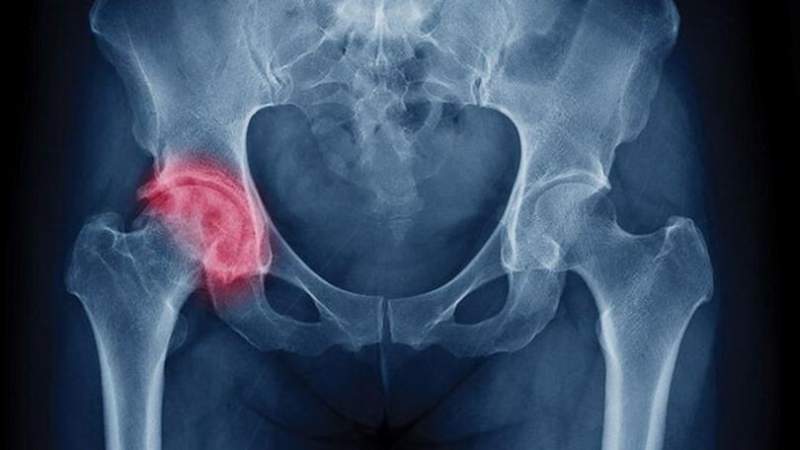

Перелом тазобедренного сустава со смещением оценивается врачами как одно из наиболее сложных повреждений, встречающихся на практике. Когда речь идет о подобной травме, то подразумевается изменение состояния целостности шейки бедра, вертлужной впадины и головки.

Анатомия сустава сложна и имеет сходство с принципом работы шарнира: головка кости находится в вертлужной впадине, капсула сустава прикреплена с одной стороны к впадине, а с другой находится несколько ниже шейки.

- капитальный перелом подразумевает перелом головки;

- субкапитальный – по основанию головки проходит отрезок надлома;

- трансцервикальный – находится в области шейки бедренной кости;

- базисцервикальный – перелом не только шейки, но еще и ее тела.